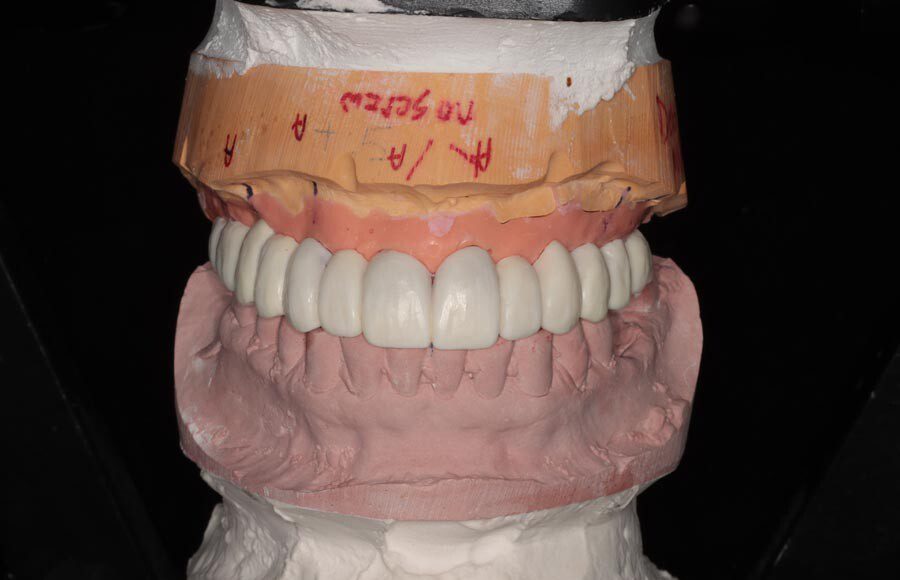

Records are sent to the dental laboratory and a prototype is designed in wax. This prototype is tried in the patient’s mouth and evaluated for fit and esthetics.

Records are sent to the dental laboratory and a prototype is designed in wax. This prototype is tried in the patient’s mouth and evaluated for fit and esthetics.

Records are sent to the dental laboratory and a prototype is designed in wax. This prototype is tried in the patient’s mouth and evaluated for fit and esthetics.